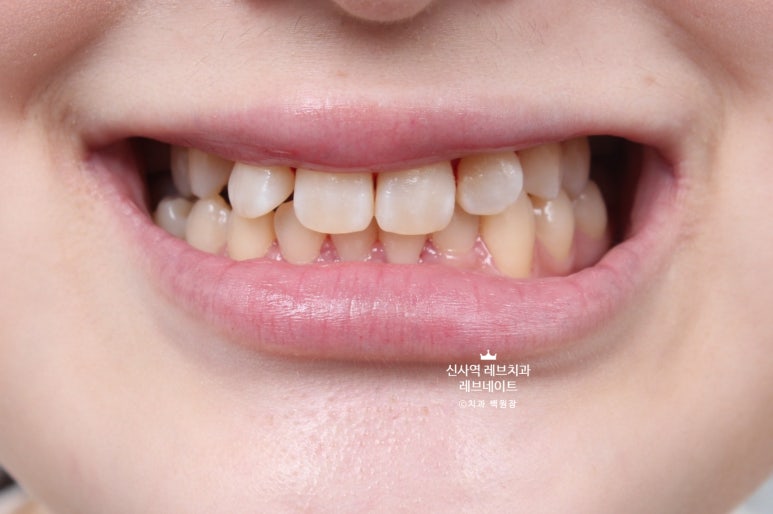

그냥 얼핏 보기엔 뭐.. 치열이 조금 틀어져 있네? 이 정도라고 생각이 드실텐데요

(저 또한 그랬습니다.)

이게 왠걸 ! 고개를 돌려보니 치아가 하나 없는겁니다...

어딨지? 하고 보니,

오른쪽 송곳니가 보다 안쪽에 있는 부정교합이라, 마치 치아하나가 없는 것 처럼 보이는 상태셨어요.

정면만 딱 보면 안보이는 것 같은데, 얘기하거나 웃을 때 엄청 잘 보이는 앞니 사이 공간이 있는거에요..

그리고 잘 보면, 치아들이 조금 뻐드러져 있기도 하고.. 뭔가 돌아가 있기도 하고..